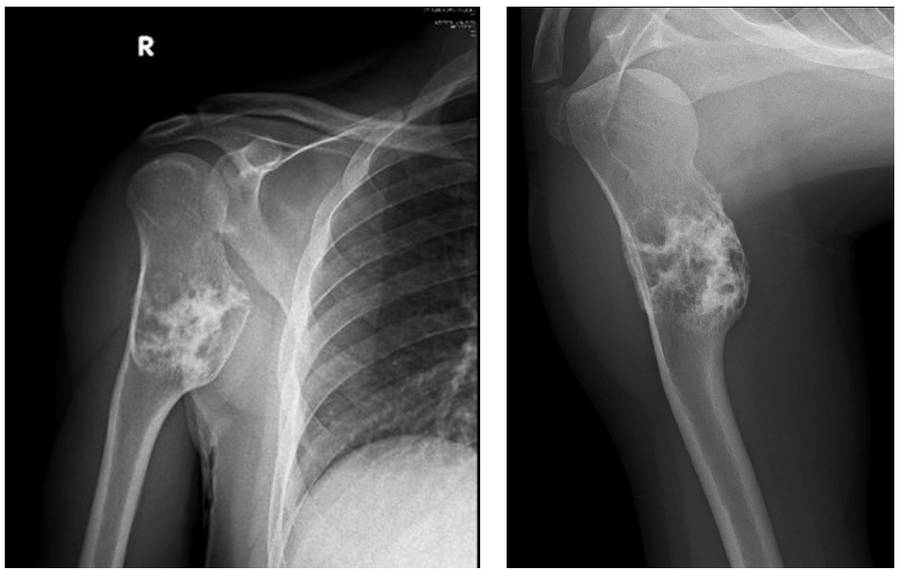

Ameliyat Öncesi: Röntgende proksimal humerusda kemikte ekspansiyona enden olan düzensiz kitle görünmekte